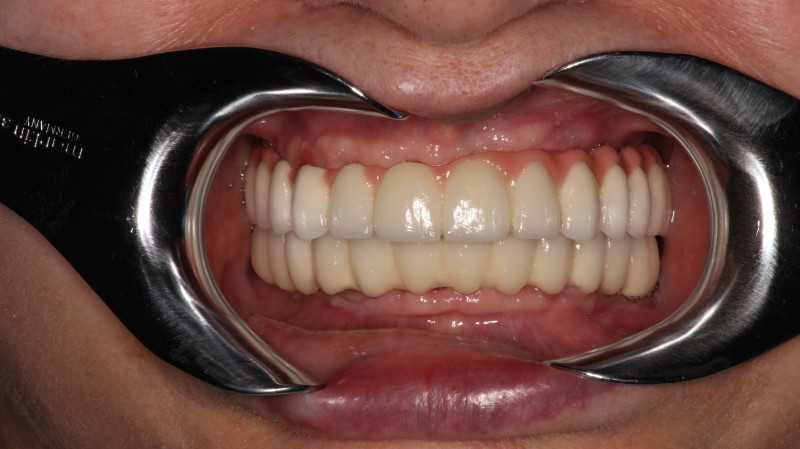

Жалобы: на отсутствие зубов, неудовлетворительную эстетику зубных рядов, невозможность жевать, снижение высоты прикуса. Что сделано: удаление зубов на в/ч и н/ч, установка имплантатов Bredent Sky и одномоментное протезирование акриловыми протезами с опорой на имплантаты по протоколу Fast & Fixed (зубы за один день). Через 8 месяцев проведена работа по замене протезов на постоянные металлокерамические. Что получил пациент: красивые и ровные зубные ряды, возможность нормально питаться с первого дня после операции, поднята высота прикуса, теперь не стесняется улыбаться.